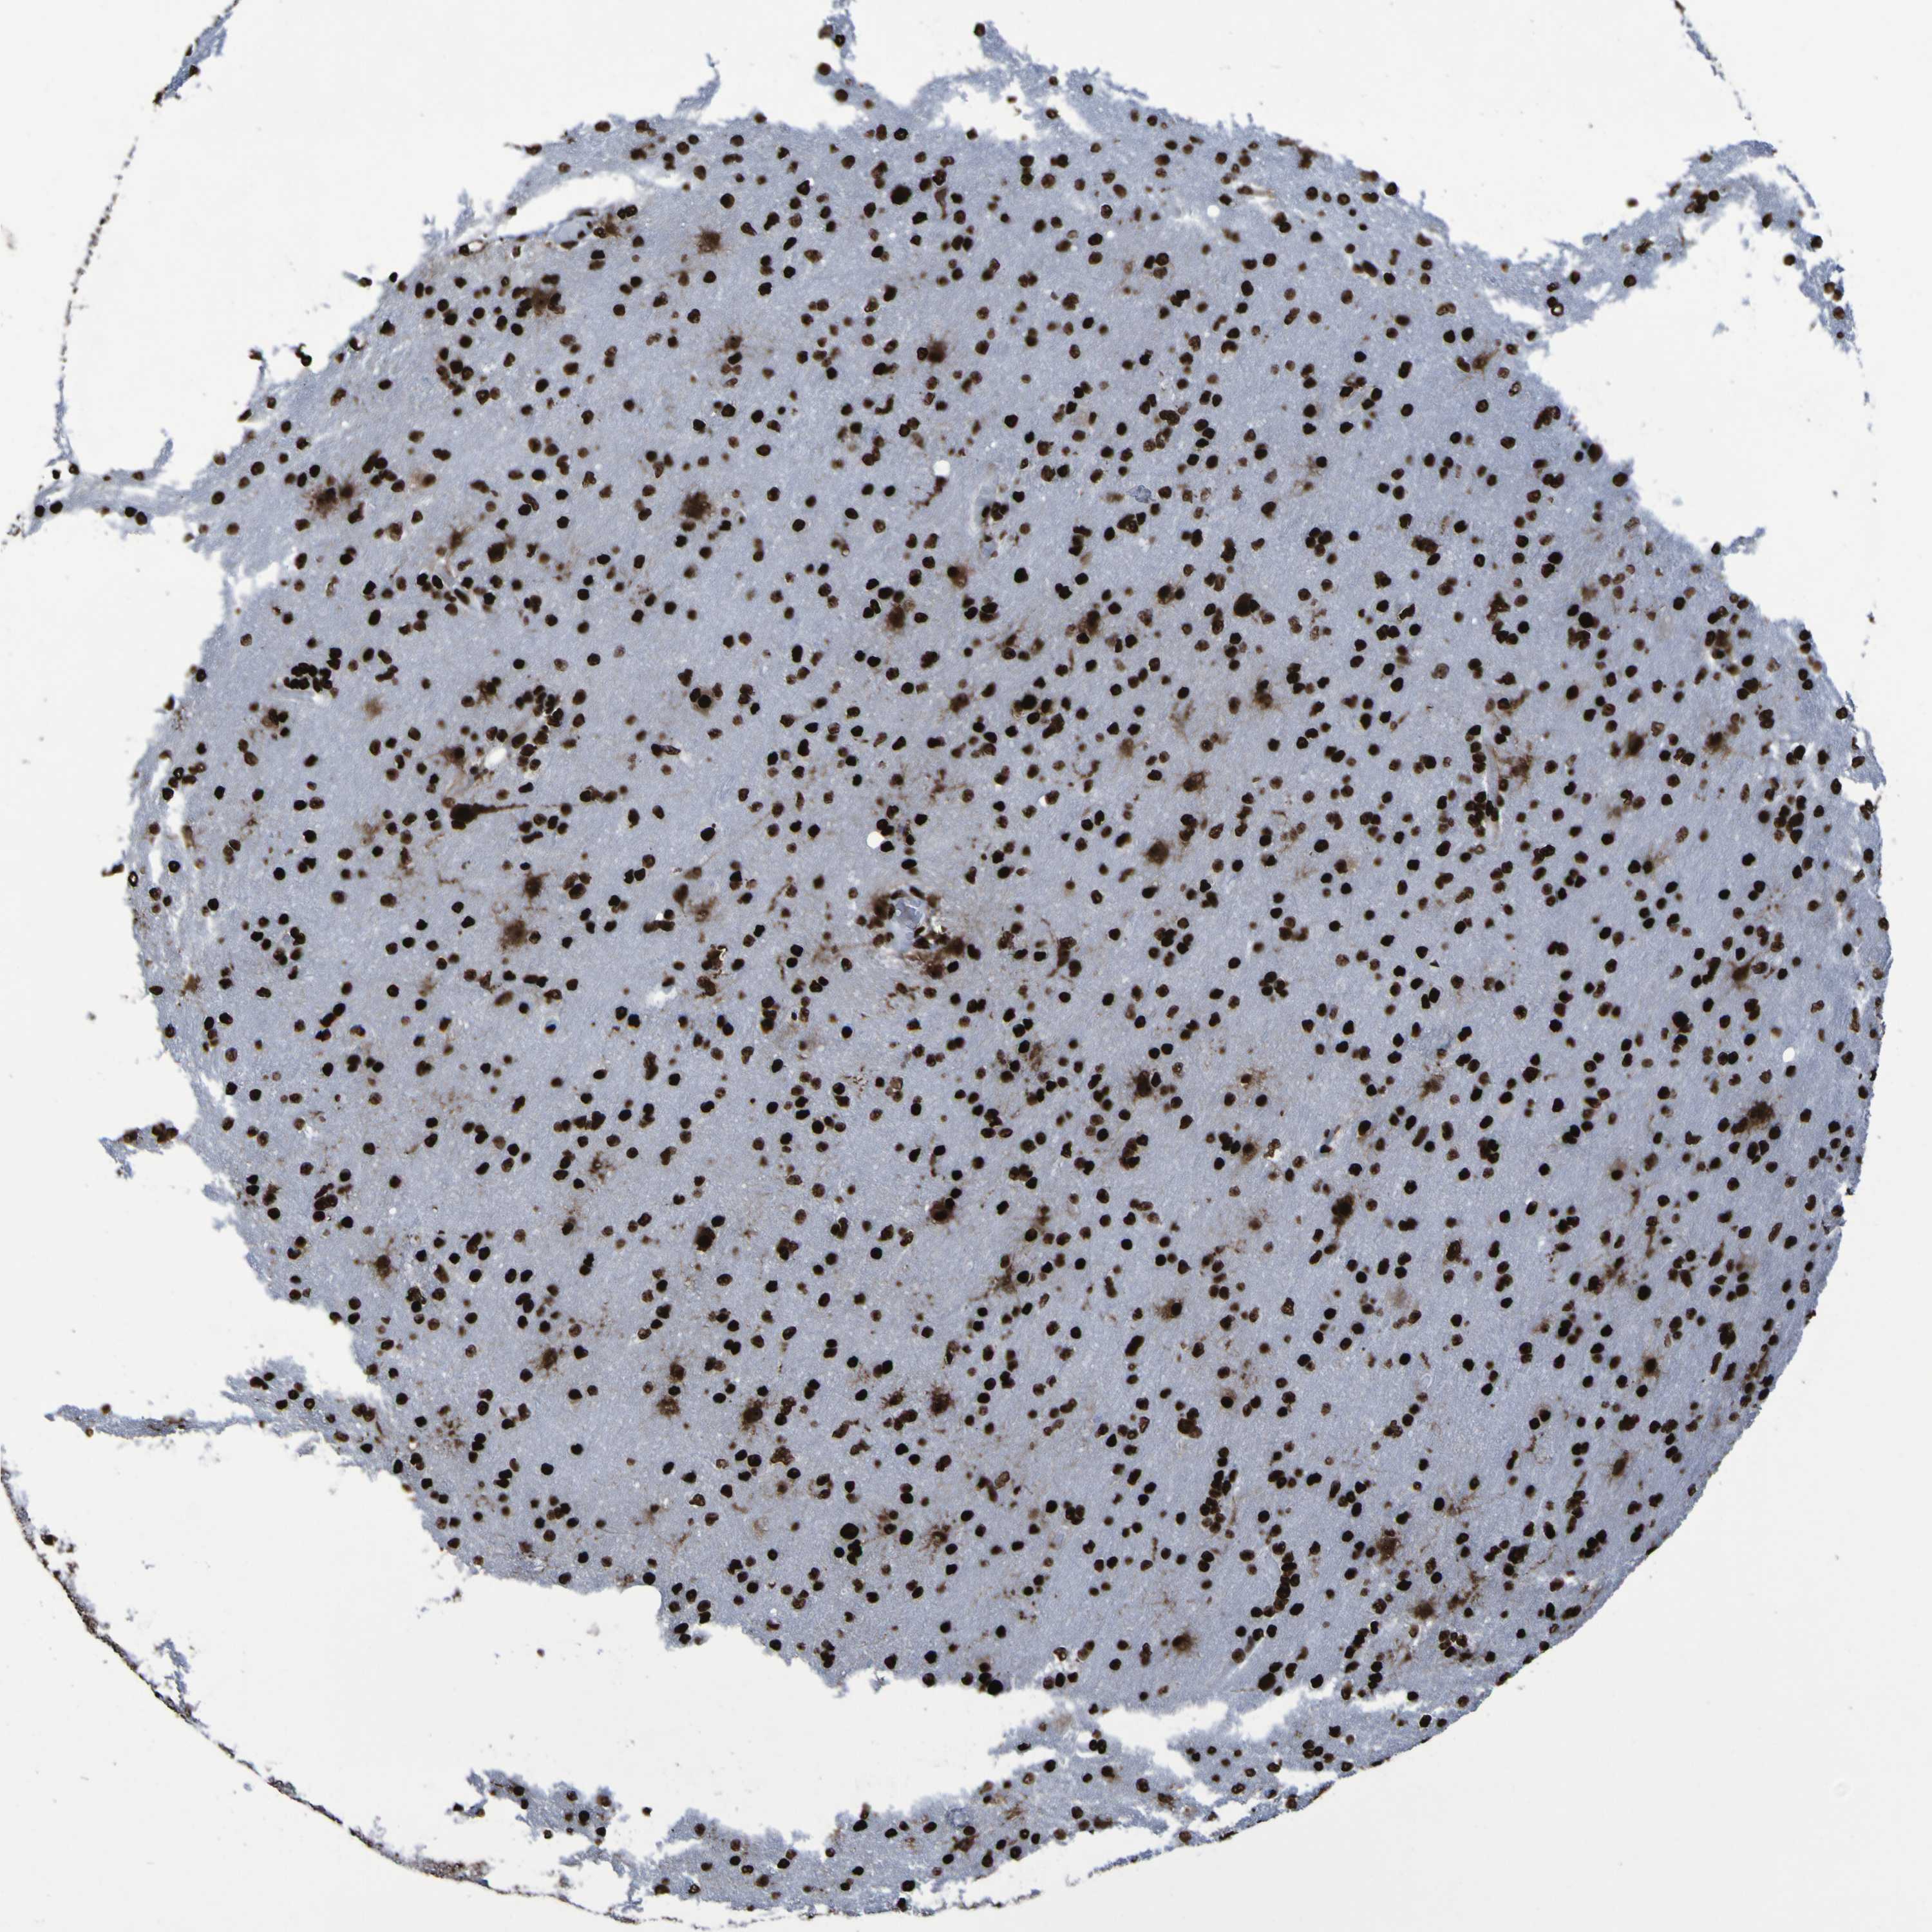

GLIOMA - Protein expressioni

A mouse-over function shows sample information and annotation data. Click on an image to view it in a full screen mode. Samples can be filtered based on level of antibody staining by selecting one or several of the following categories: high, medium, low and not detected. The assay and annotation is described here.

Note that samples used for immunohistochemistry by the Human Protein Atlas do not correspond to samples in the TCGA dataset.

Antibody stainingi

Antibody staining in the annotated cell types in the current human tissue is reported as not detected, low, medium, or high, based on conventional immunohistochemistry profiling in selected tissues. This score is based on the combination of the staining intensity and fraction of stained cells.

Each image is clickable and will lead to virtual microscopy that enables deeper exploration of all samples and also displays staining intensity scores, fraction scores and subcellular localization as well as patient and tissue information for each sample.

Antibody HPA011384

Antibody CAB012983

Staining

High

Medium

Low

Not detected

Intensity

Strong

Moderate

Weak

Negative

Quantity

>75%

75%-25%

<25%

None

Location

Nuclear

Cytoplasmic/membranous

Cytoplasmic/membranous,nuclear

Glioma, malignant, High grade

Glioma, malignant, Low grade